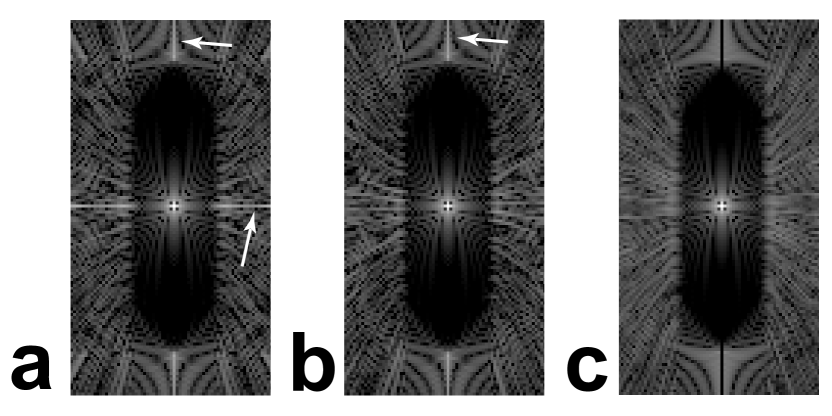

Refer to caption

Figure 6: Projection sampling patterns (left column) and PSFs (middle column), with plots along x𝑥x (black, dashed line) and y𝑦y (gray line) axes in the right column. FOV shapes: (a) Circle, (b) Ellipse, (c) Rectangle, (d) Oval, and (e) Diamond. The inset PSF images are windowed narrowly to show the low-level aliasing (arrows) within the desired FOV (dashed lines). The plots show the aliasing peaks and the isotropic resolution in the central lobes. Small FOVs are used for visualization of the variable angular density.

IV-A 2D PSFs

Figure 6 shows some sampling patterns designed with the 2D anisotropic FOV algorithm and their corresponding PSFs, showing that the desired FOV shapes are achieved. They have isotropic resolution, as shown in the PSF central lobes. There is some low-level aliasing introduced inside the desired FOV for the anisotropic shapes, shown in the inset PSF images. See Section V for a full discussion.